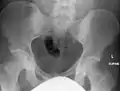

Osteopoikilosis of the hips on CT.

The radiographic appearance of osteopoikilosis on an X-ray is characterized by a pattern of numerous white densities of similar size spread throughout all the bones. This is a systemic condition. It must be differentiated from blastic metastasis, which can also present radiographically as white densities interspersed throughout bone. Blastic metastasis tends to present with larger and more irregular densities in less of a uniform pattern. Another differentiating factor is age, with blastic metastasis mostly affecting older people, and osteopoikilosis being found in people 20 years of age and younger.

The distribution is variable, though it does not tend to affect the ribs, spine, or skull.[2]